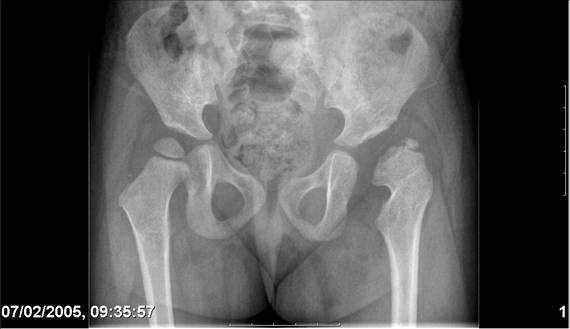

Здравствуйте, уважаемые коллеги.Обратилась девочка 6-ти лет из жалобами на боль в левом т/б суставе,хромоту Из анамнеза : ребенок лечился с рождения по поводу врожденного вывиха бедер. В возрасте 3- х лет в одной из клиник была выполнена остеотомия таза по Пембертону и варизирующая остеотомия бедра слева, справа - остеотомия таза по Солтеру и остеотомия бедра. Посоветуйте тактику лечения. С уважением Ihor

Smotritsya parshivo konechno(pseudoacetabulum,partial AVN), no v6 let ya by popytalsya ispravit chto moghno:shortening (ne boyatsya ubrat bolshoi fragment),derotation(30 gradusov ne bolshe)+pelvic osteotomy in true acetabuluam area.Obyazatelno takghe open reduction with wide capsular exposure.

Navernoe Dega

Chto by ne byt goloslovnym posilau vam svoi sluchai gde sdelal vse chto napisal vyshe

Уважаемой Ihor! Следует дообследовать ребенка, проведя РКТ или МРТ. Необходимо установить взаимоотношение головки бедренной кости и вертлужной впадины слева, оценить угол антеторсии и истинный ШДУ. Далее решать вопрос об оперативном лечении. Скорее всего показана деторсионно-варизирующая остеотомия в межвертельной области левого бедра и остеотомия таза типа Солтера (хотя ацетабулярный индекс великоват, т.е. более 30-35 градусов). Справа следует понаблюдать и периодически проводить курсы ФТО и ЛФК. Если Вы не имеете опыта реконструктивной хирургии ТБС у детей, то лучше отправить пациента к детским ортопедам. АИФ